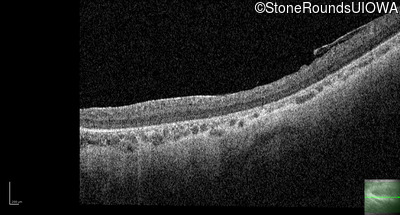

Optical Coherence Tomography - Right - 10/300 sc

Exemplar / OCT Stack